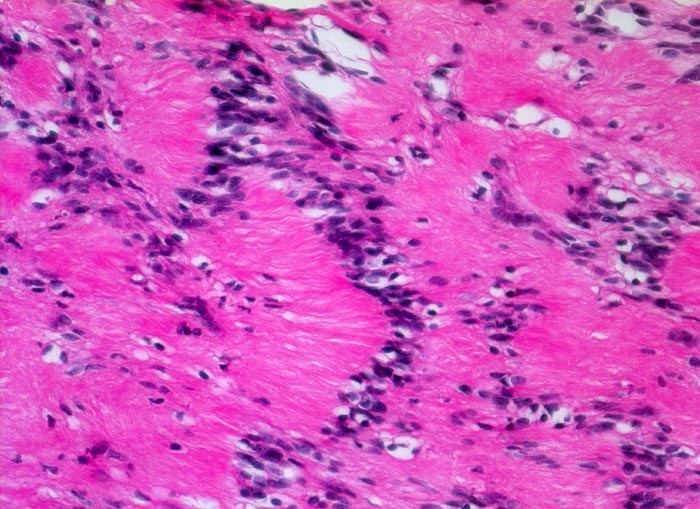

Die histomorphologischen Befunde sind sehr variabel. Am häufigsten bestehen die Tumoren aus Zellzügen mit bipolar orientierten länglichen oder gewellten Kernen und langen Zellfortsätzen. In den sogenannten Antoni A Arealen (> 4295) sind die Zellen in kompakten Bündeln angeordnet, teilweise in Form von Verocay bodies (> 493) (alternierende Anordnung von Kernreihen und Zellfortsätzen). In den Antoni B (> 4296) Arealen bilden die Fortsätze der eher sternförmigen Tumorzellen ein lockeres Geflecht. Einzelne grosse, unregelmässig geformte und hyperchromatische Kerne und flächenhafte Nekrosen, Hyalinisierung oder fokale Verkalkungen sind Ausdruck degenerativer Veränderungen (sogenanntes ancient schwannoma (> 4299)) und dürfen nicht als Zeichen der Malignität fehlinterpretiert werden.

• Antoni A Muster: Parallele Anordnung der Zellkerne und Zellfortsätze (Verocay bodies).